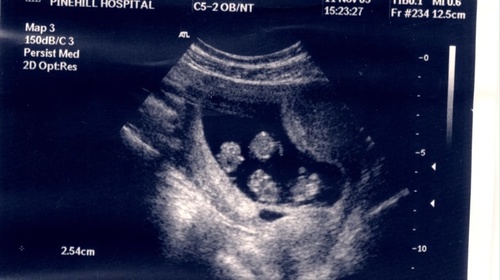

Chiar înainte să facă fertilizare in vitro, a rămas gravidă cu cvadrupleţi identici. “Le scriam iniţiala numelui pe talpă”